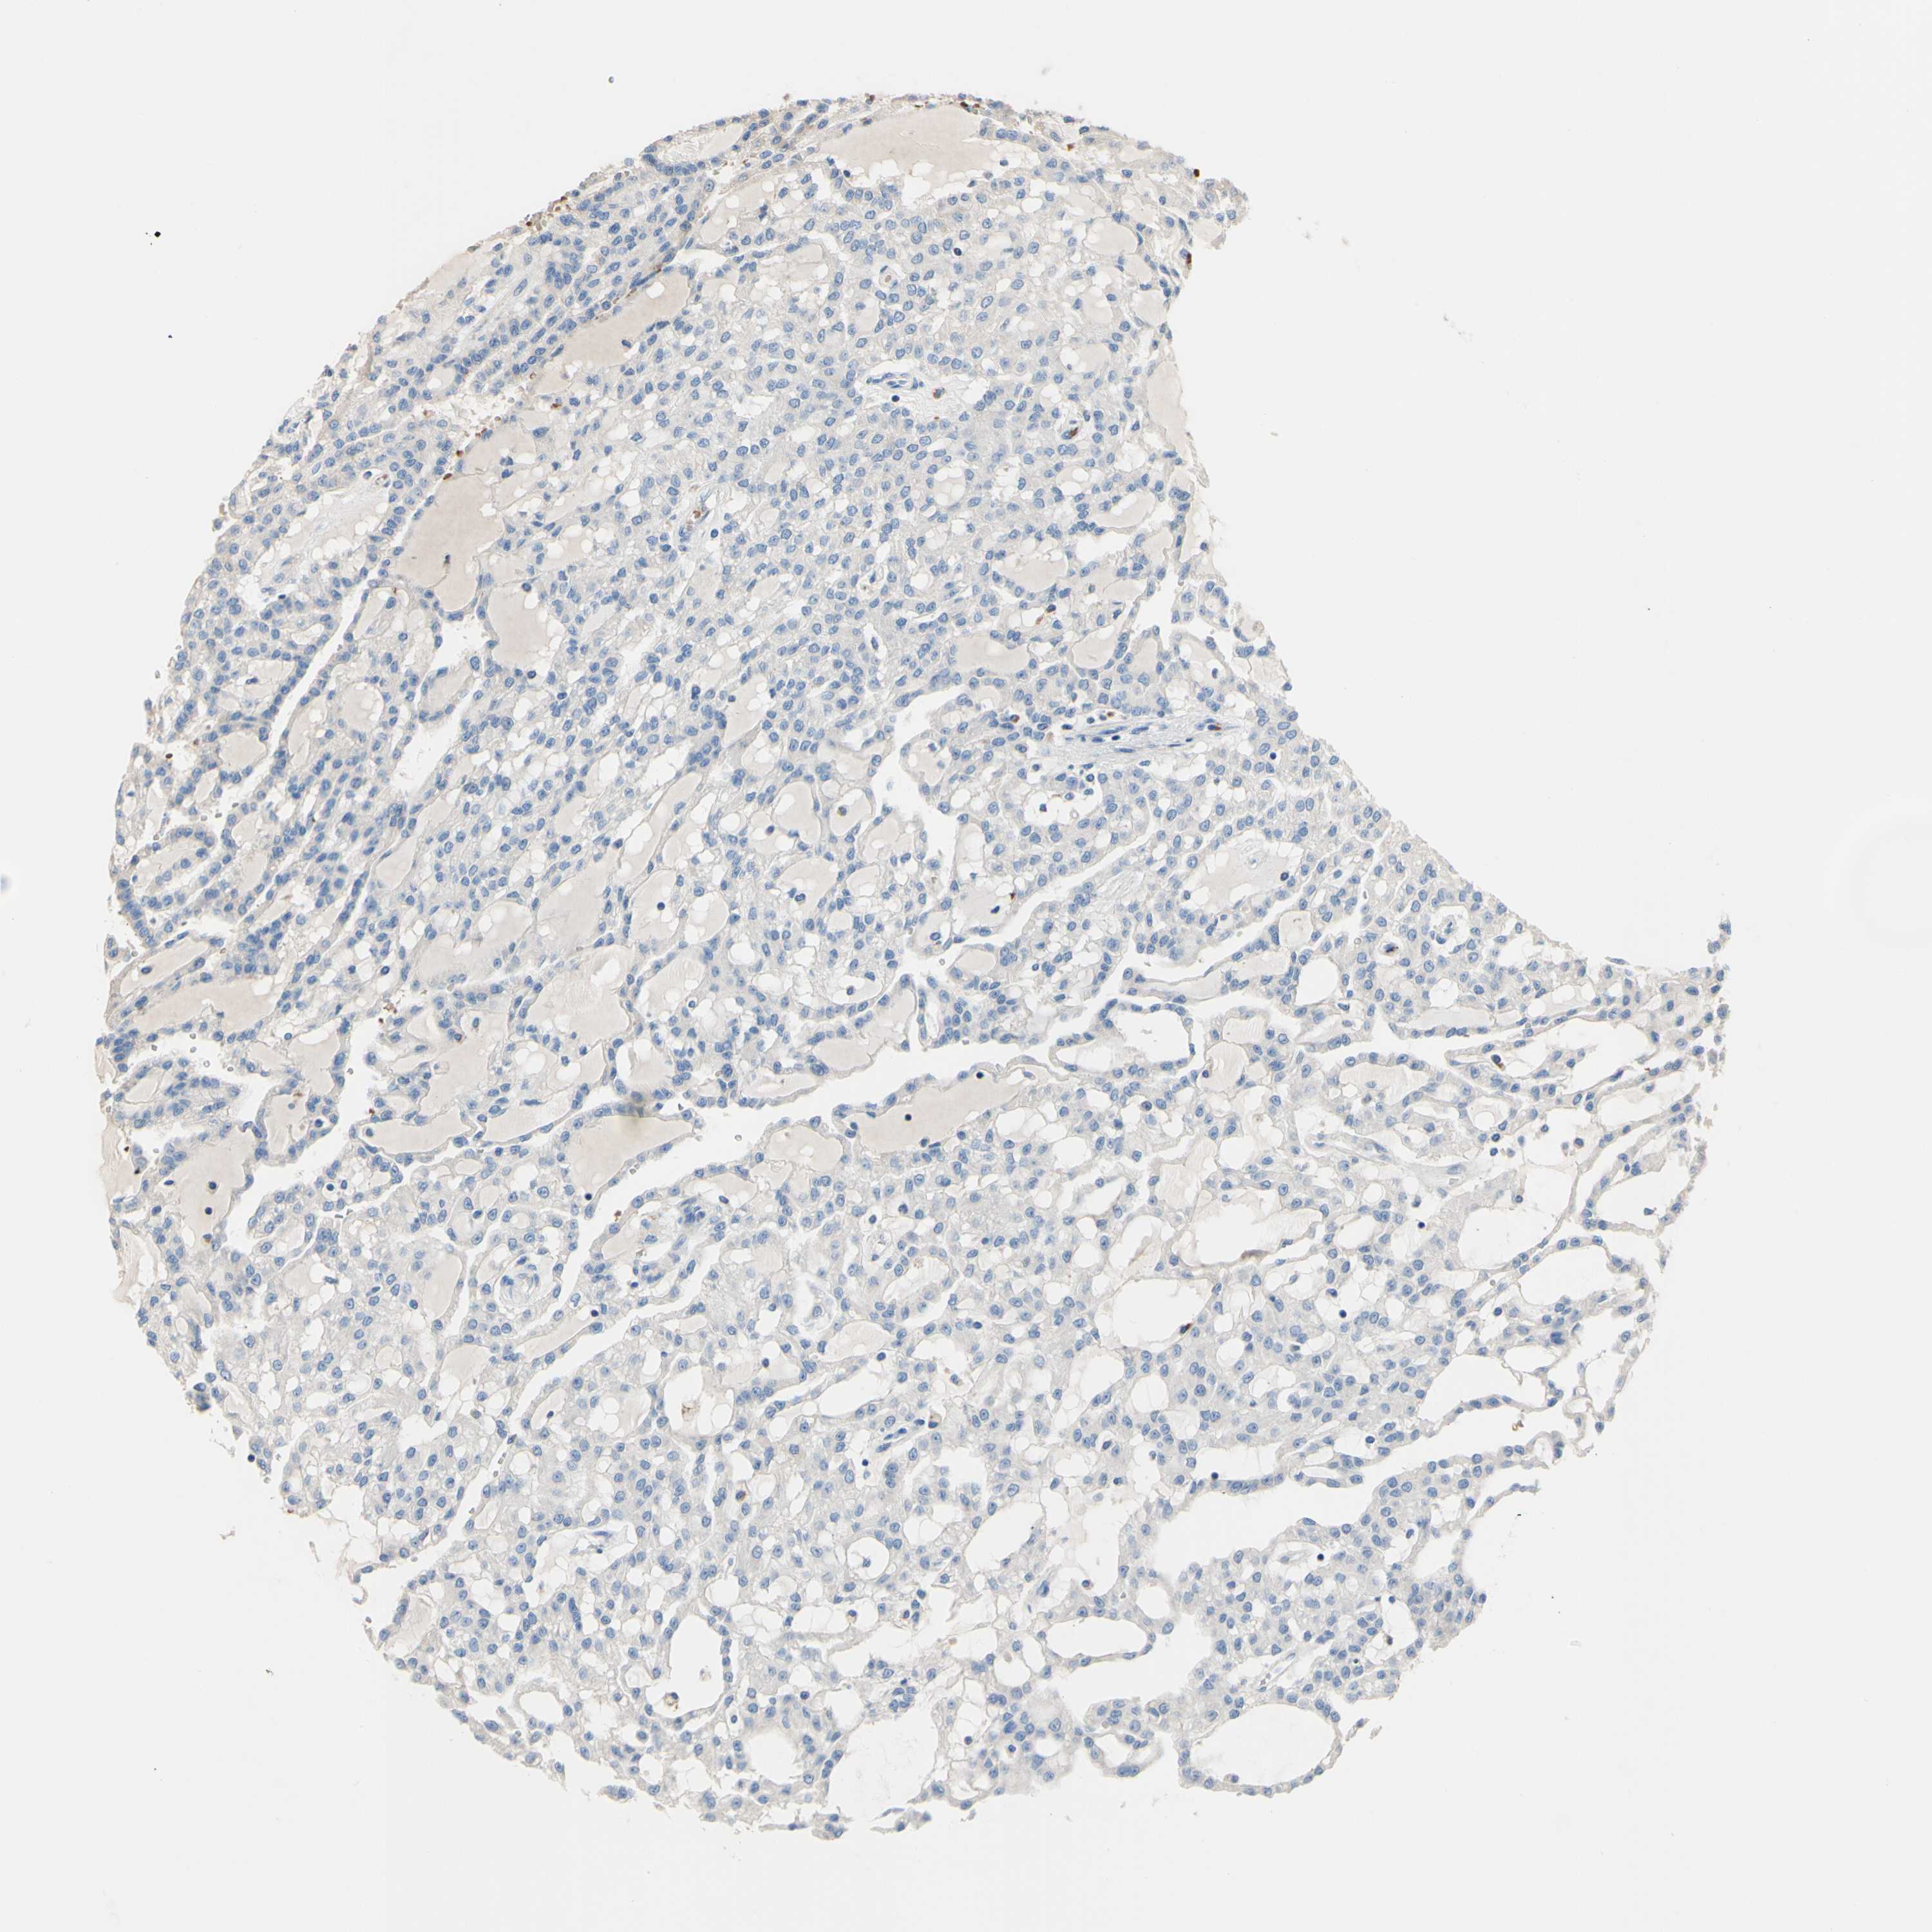

KIDNEY RENAL CLEAR CELL CARCINOMA (VALIDATION) - Interactive survival scatter ploti

The Survival Scatter plot shows the clinical status (i.e. dead or alive) for all individuals in the patient cohort, based on the same data that underlies the corresponding Kaplan-Meier plots. Patients that are alive at last time for follow-up are shown in blue and patients who have died during the study are shown in red.

The x-axis shows the expression levels (FPKM) of the investigated gene in the tumor tissue at the time of diagnosis. The y-axis shows the follow-up time after diagnosis (years). Both axes are complimented with kernel density curves demonstrating the data density over the axes. The top density plot shows the expression levels (FPKM) distribution among dead (red) and alive patients (blue). The right density plot shows the data density of the survived years of dead patients with high and low expression levels respectively, stratified using the cutoff indicated by the vertical dashed line through the Survival Scatter plot. This cutoff is automatically defined based on the FPKM cutoff that minimizes the p-score. The cutoff can be changed by dragging the vertical line or by entering a cutoff value in the square labeled "Current cut-off".

Under the Survival Scatter plot the p-score landscape (black curve; left axis) is shown together with dead median separation (red curve; right axis). Dead median separation is the difference in median mRNA expression between patients who have died with high and low expression, respectively. It is calculated as follows: median FPKM expression of dead patients with high expression - median FPKM expression of dead patients with low expression. This is intended to aid the user in visually exploring custom cutoffs and the associated p-scores and dead median separation.

Individual patient data is displayed and can be filtered by clicking on one or more of the category buttons on the top of the page. Categories describing expression level and patient information include: high, low, alive, dead, female, male and tumor stages. The scale of the x-axis can be toggled between linear and log-scale by clicking on the "x log" button. Mouse-over function shows TCGA ID, patient information and mRNA expression (FPKM) for each patient.

& Survival analysisi

Kaplan-Meier plots summarize results from analysis of correlation between mRNA expression level and patient survival. Patients were divided based on level of expression into one of the two groups "low" (under cut off) or "high" (over cut off). X-axis shows time for survival (years) and y-axis shows the probability of survival, where 1.0 corresponds to 100 percent.

CDON is not prognostic in Kidney Renal Clear Cell Carcinoma (validation)

Best expression cut offi

Based on the FPKM value of each gene, patients were classified into two groups and association between prognosis (survival) and gene expression (FPKM) was examined. The best expression cut-off refers the FPKM value that yields maximal difference with regard to survival between the two groups at the lowest log-rank P-value. Best expression cut-off was selected based on survival analysis .

When clicking on this number, the vertical dashed line indicating cut-off, the interactive survival plot, and the Kaplan-Meier curve will be adjusted to show results based on the best expression cut-off.

: 6.36

P scorei

Log-rank P value for Kaplan-Meier plot showing results from analysis of correlation between mRNA expression level and patient survival.

N/A

TCGA RNA samplesi

RNA-seq data is reported as average FPKM (number Fragments Per Kilobase of exon per Million reads), generated by the The Cancer Genome Atlas (TCGA) .

Normal distribution across the dataset is visualized with box plots, shown as median and 25th and 75th percentiles. Points are displayed as outliers if they are above or below 1.5 times the interquartile range. FPKM values of the individual samples are presented next to the box plot.

Average pTPM 5.1

Number of samples 100